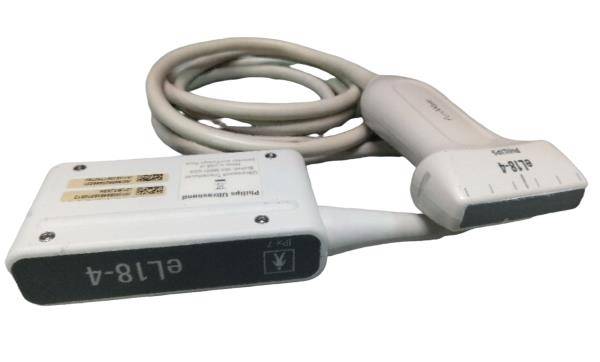

Seller Notes:âThe unit is in good cosmetic condition with some signs of wear and tear consistent with normal use (See Pictures). The unit was tested at our facility and found to be in good working order. Samsung Medison 3D 2-6ET 3D/4/D Convex Probe Bandwidth: 2 â 6 MHz Applications: Abdomen, Obstetrics, Obstetrics Early, Gynecology, Fetal Heart S/N: 275-K-A330Aâ